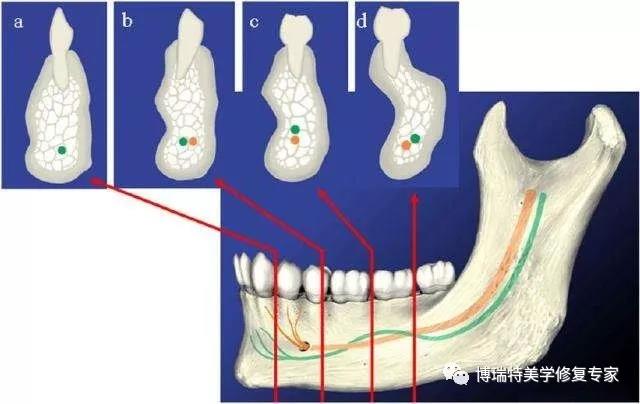

2.下牙槽神经移位术

下牙槽神经移位术多用于下颌后牙区种植。下颌骨牙槽突骨吸收的速度是上颌骨的4倍,下颌后牙区缺牙后,牙槽骨逐渐吸收,高度降低,下颌管与牙槽嵴顶之间的距离缩小,可用骨小于种植体植入的最低要求(6 mm),由于种植区骨量不足,限制了种植义齿修复的适用范围。此时若强行种植不仅难以取得种植体的初期稳定性,而且易损伤下牙槽神经造成下唇麻木。为避免损伤下牙槽神经,通过下牙槽神经移位术,解剖出下牙槽神经,从而为种植体的植入提供了空间。

下牙槽神经移位术最为常见的并发症为下唇麻木,通常为神经损伤所致。Seddon等:将神经损伤分为神经牵拉和神经断裂,其区别为轴索的连续性,若轴索的连续性得以保存,则神经只是受到了牵拉,损伤是暂时的,可予以营养神经的药物,一般4个月内达到恢复。若轴索断裂,此时则应及早实施下牙槽神经吻合术。